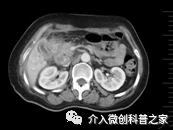

中晚期胰头癌侵及胆总管行胆道支架植入治疗

(梗阻性黄疸即可解除)